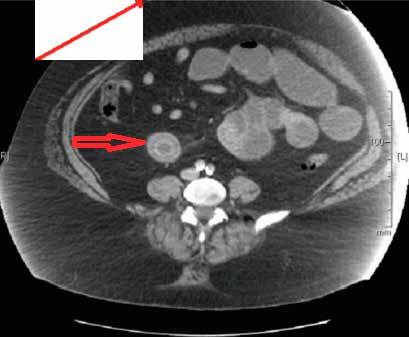

一名49岁的女性患者因上腹部疼痛伴恶性呕吐于当地医院急诊科就诊,两个月前患者因胆石症,胆总管扩张,梗阻性黄疸行内镜逆行行胰胆管造影术,,取出3块胆石,如图1、2。行腹部CT检查,提示小肠梗阻,胆石性肠梗阻,十二指肠瘘,如图3、4。患者立即行急诊手术治疗,术中发现扩张小肠有明显胆石阻塞及压迫痕迹,取出胆石,由于小肠压力过大,出现部分坏死,因此行小肠部分切除术,如图5。在距离回盲部60cm小肠处取出大小约3.5cm*3.5cm胆结石,如图3。用腹腔镜从Treitz韧带检查小肠,并未发现有残余结石,病人在手术后已康复,顺利出院。

图3 腹部CT提示小肠内存在结石